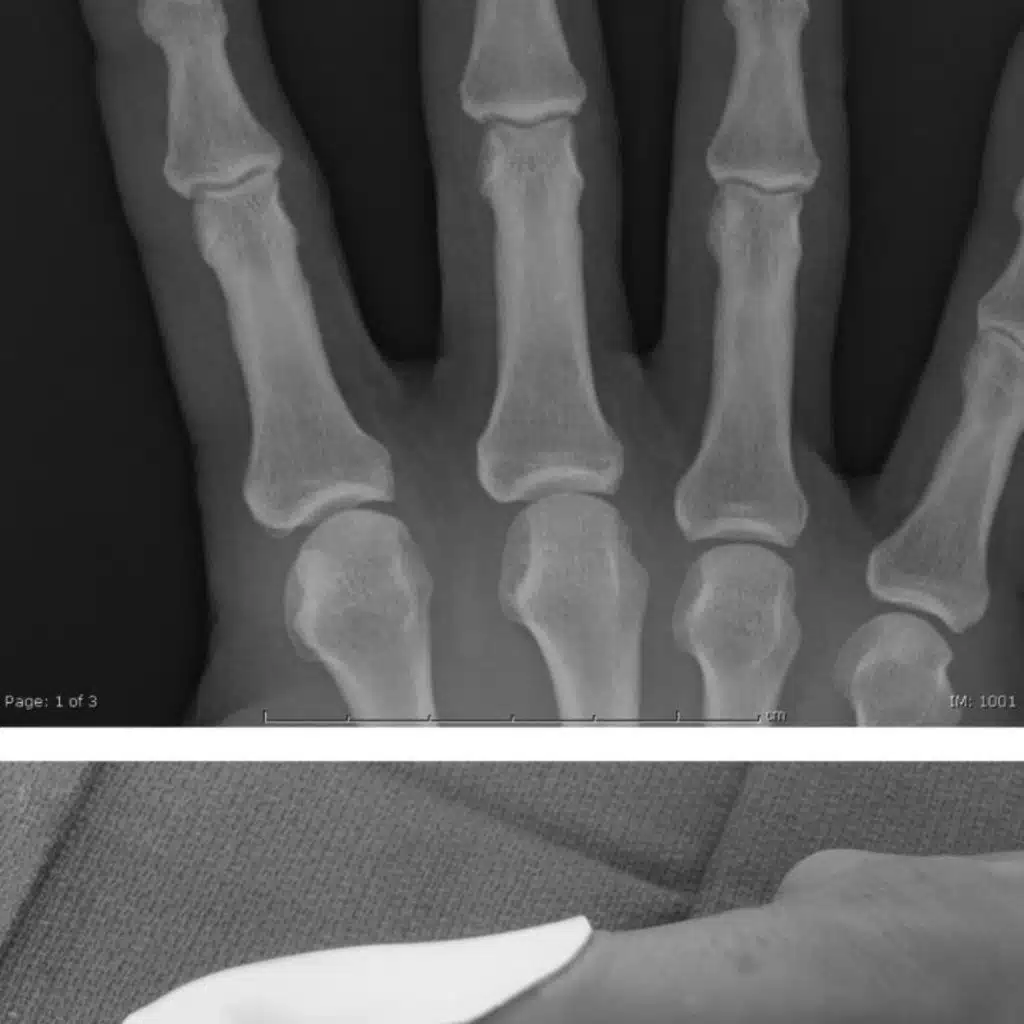

Extra-Octave Fracture

Mims L et al. Extra-Octave Fracture in a 14-Year-Old Basketball Player. Journal of Pediatrics. 2017; 186: P206-206

Same boy, after reduction and ulnar splint

Same boy, on follow-up at 17 days